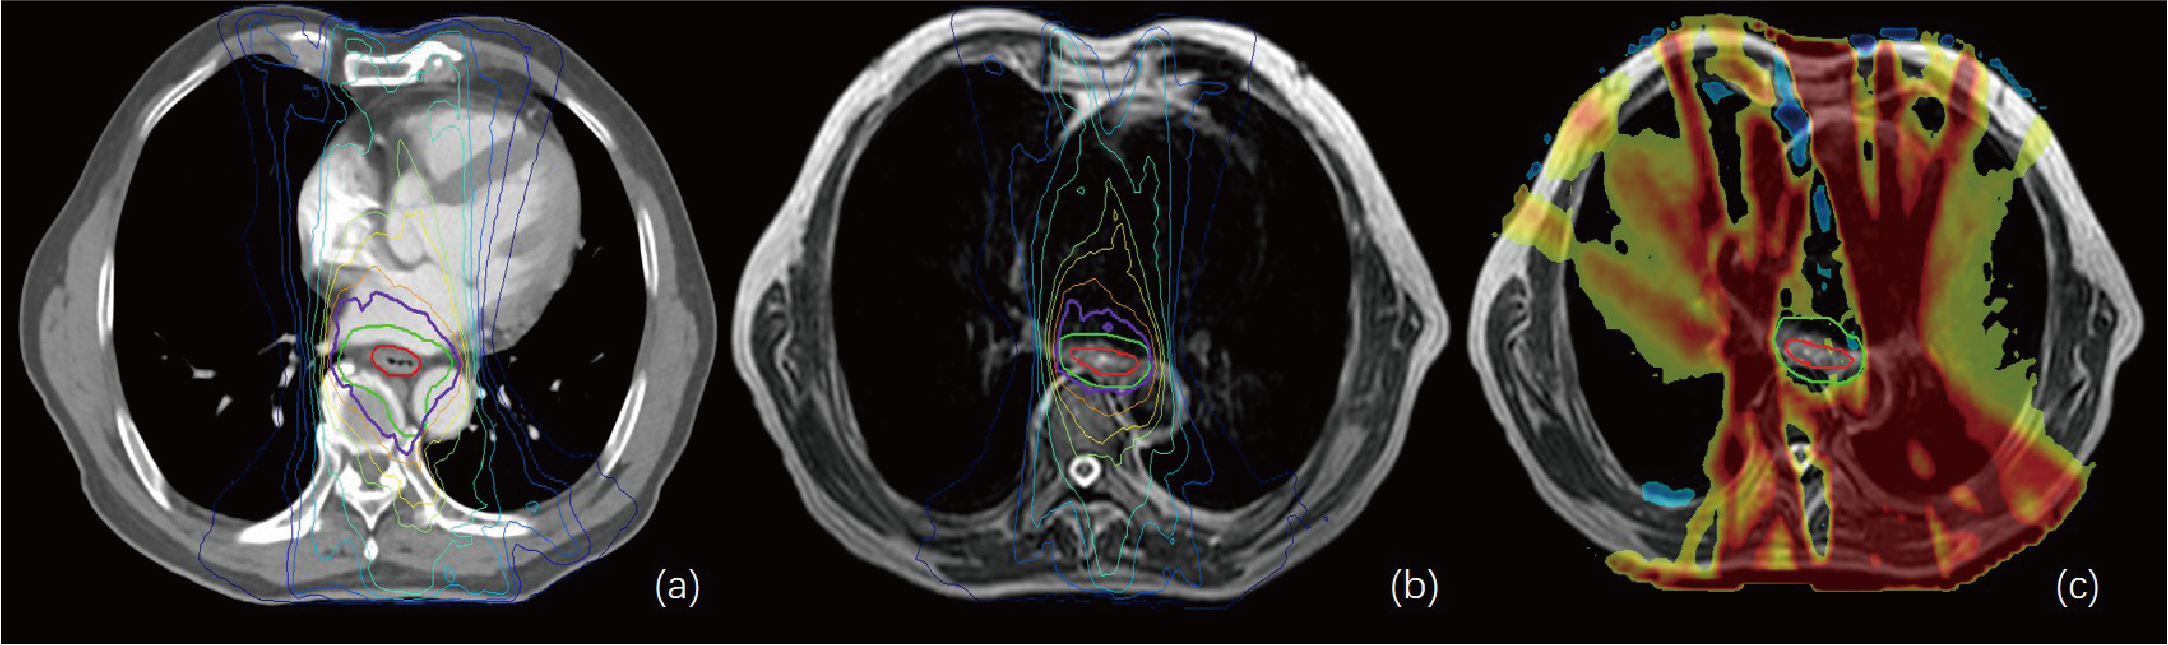

Figure 4

(A, B) show the isodose curves of the adapt-to-position (ATP) and adapt-to-shape (ATS) plans, respectively. (C) indicates the ATP dose minus the ATS dose. The red line represents the gross target volume (GTV), and the green line represents the planning target (PTV). This figure shows that the OAR lung and heart doses in the ATS plan were significantly smaller than those in the ATP plan, while the target–volume PTV dose was similar or slightly increased.